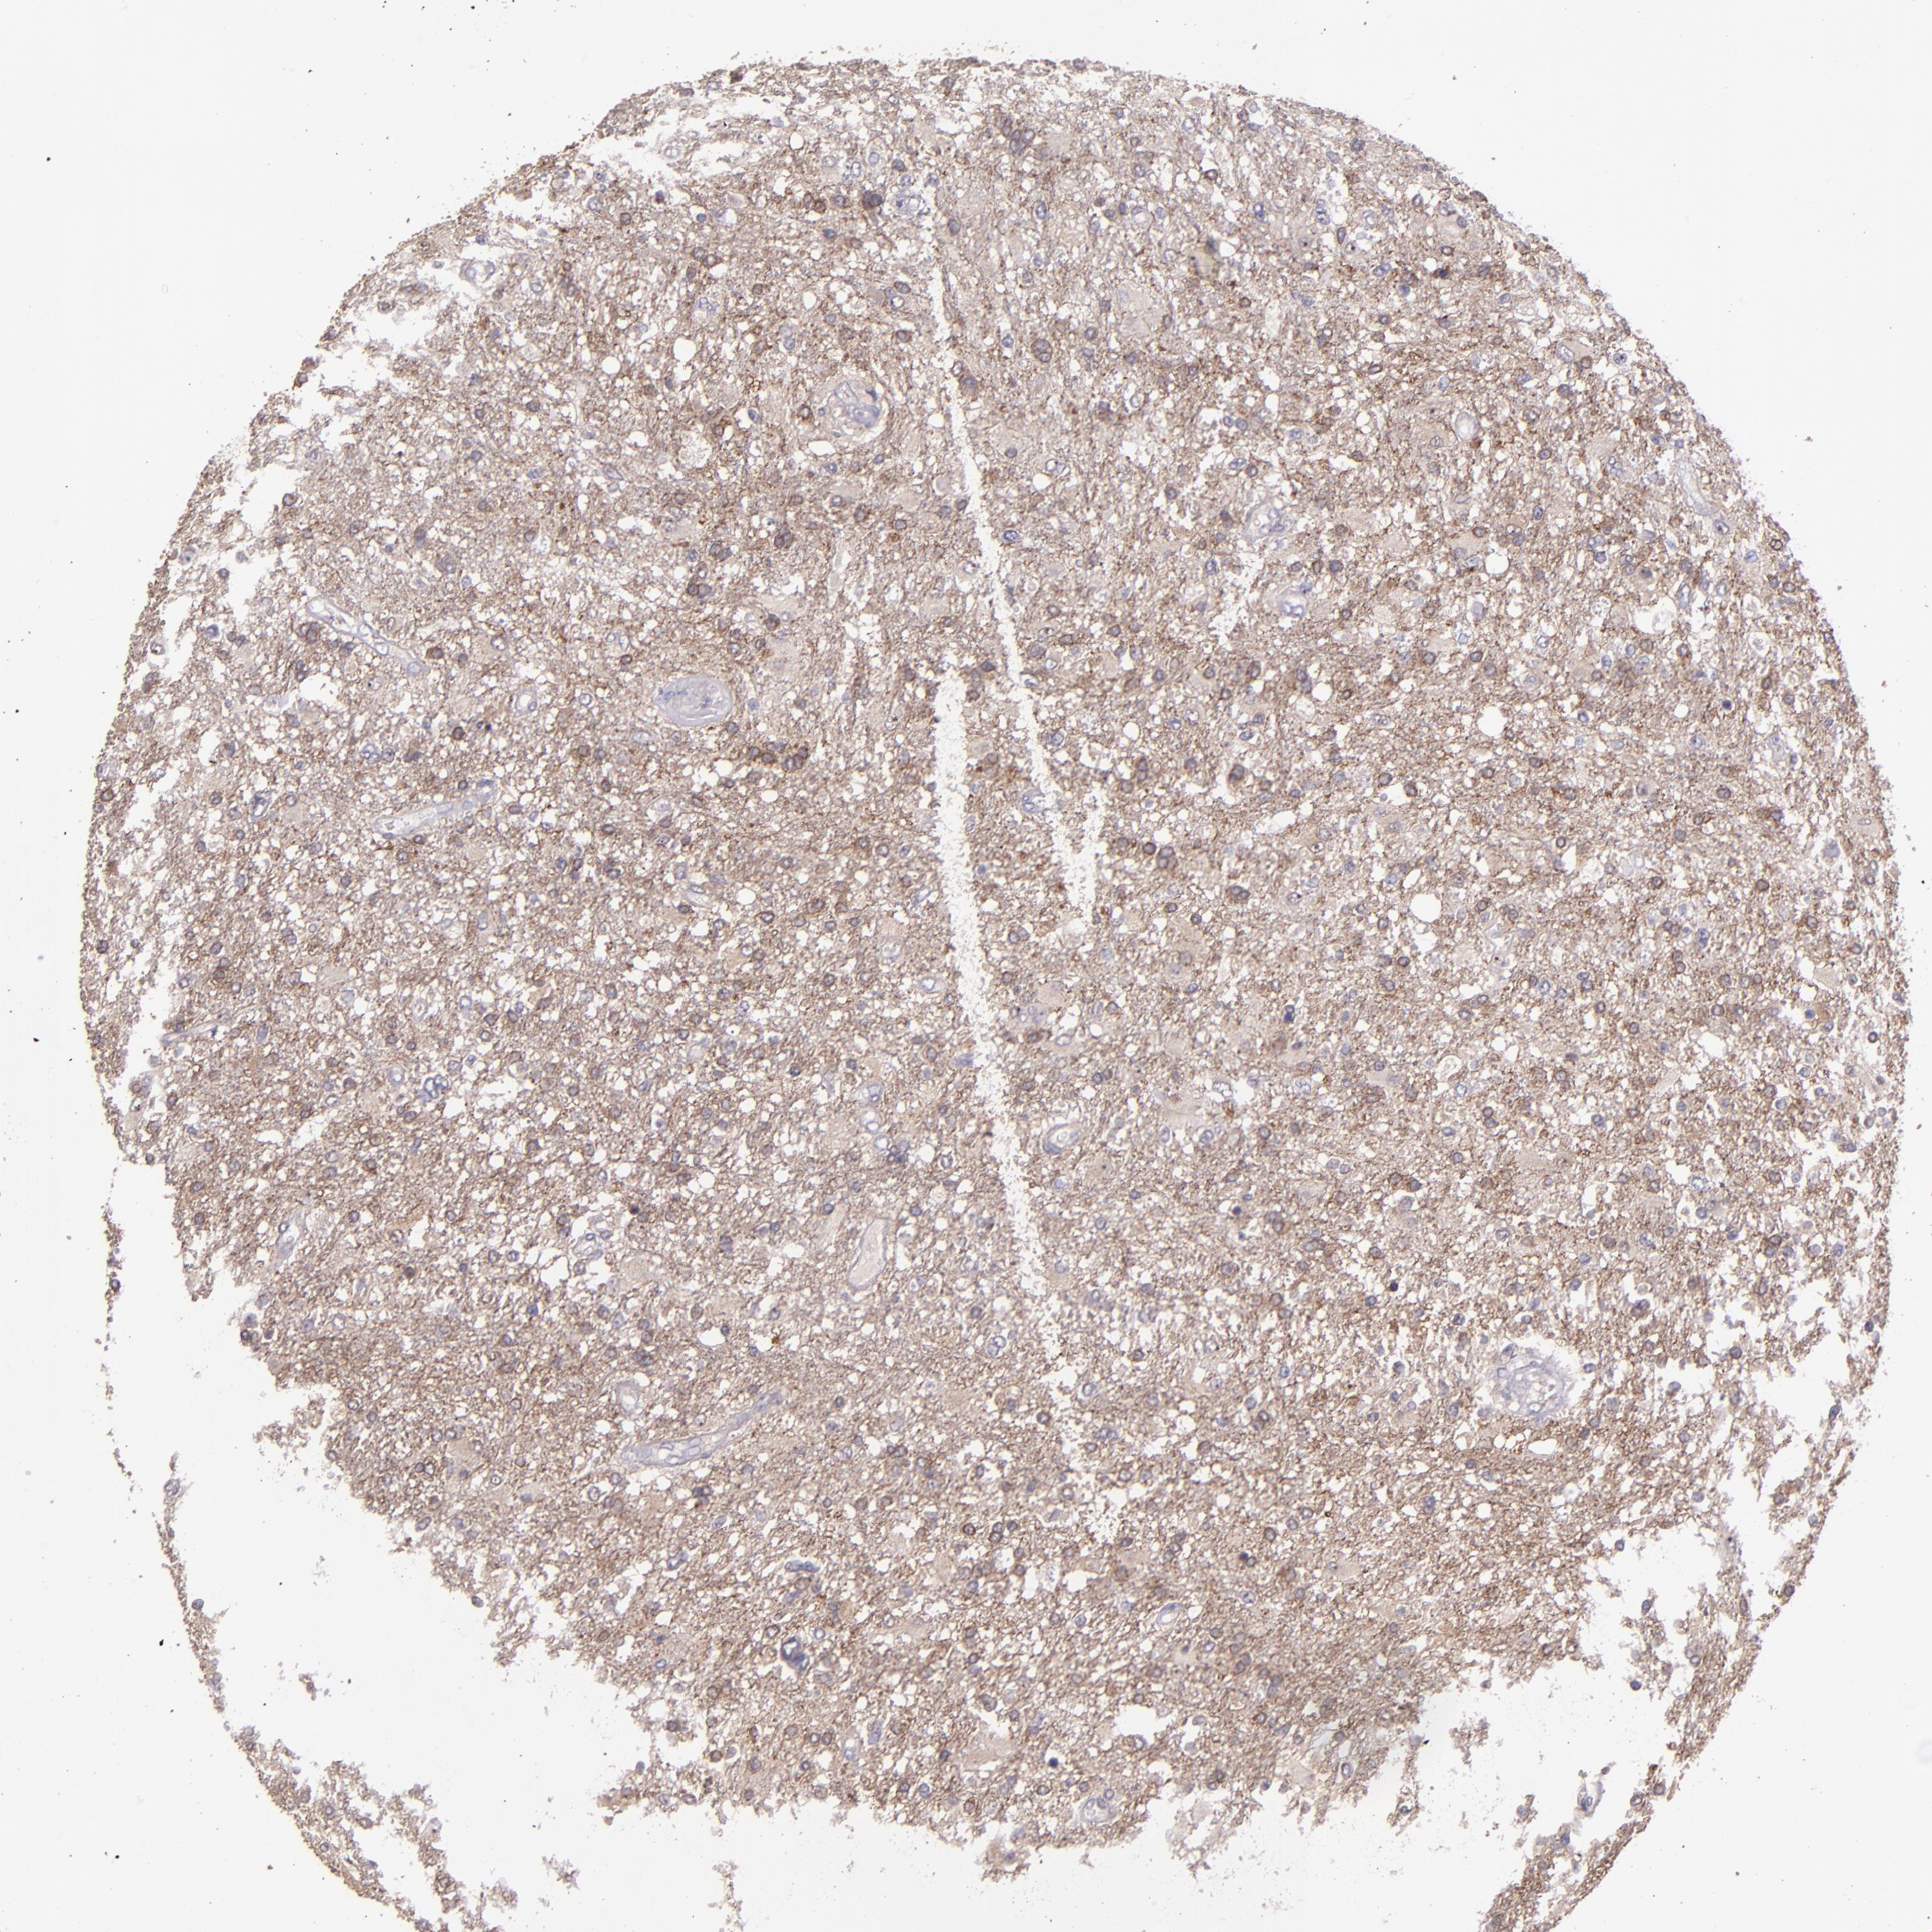

GLIOMA - Protein expressioni

A mouse-over function shows sample information and annotation data. Click on an image to view it in a full screen mode. Samples can be filtered based on level of antibody staining by selecting one or several of the following categories: high, medium, low and not detected. The assay and annotation is described here.

Note that samples used for immunohistochemistry by the Human Protein Atlas do not correspond to samples in the TCGA dataset.

Antibody stainingi

Antibody staining in the annotated cell types in the current human tissue is reported as not detected, low, medium, or high, based on conventional immunohistochemistry profiling in selected tissues. This score is based on the combination of the staining intensity and fraction of stained cells.

Each image is clickable and will lead to virtual microscopy that enables deeper exploration of all samples and also displays staining intensity scores, fraction scores and subcellular localization as well as patient and tissue information for each sample.

Antibody HPA001667

Antibody CAB016724

Staining

High

Medium

Low

Not detected

Intensity

Strong

Moderate

Weak

Negative

Quantity

>75%

75%-25%

<25%

None

Location

Nuclear

Cytoplasmic/membranous

Cytoplasmic/membranous,nuclear

Glioma, malignant, High grade

Glioma, malignant, Low grade

Glioma, malignant, NOS